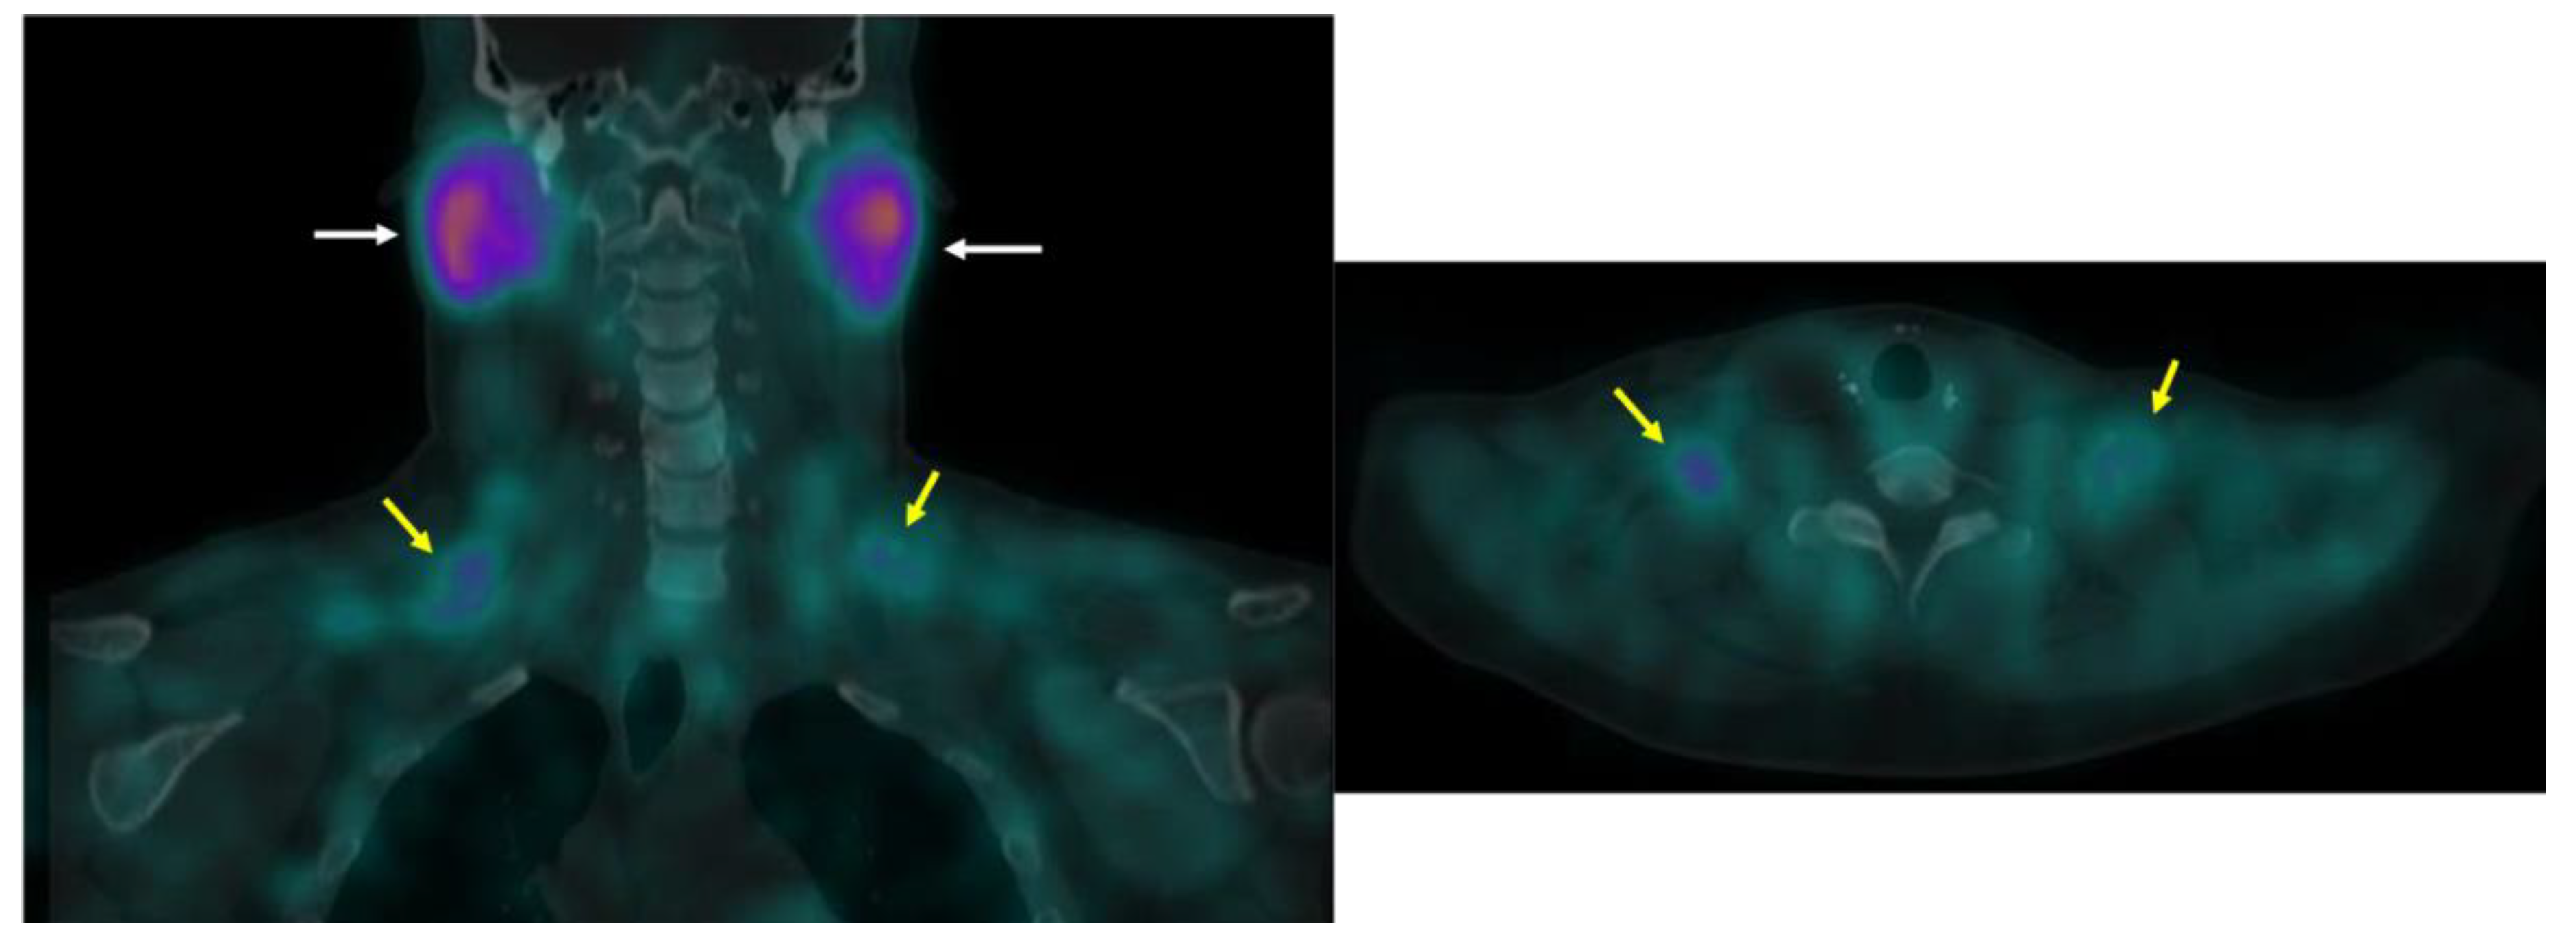

Figure 9.

99mTc-MIBI uptake in iBAT on a clinical scan. Supraclavicular BAT uptake shown coronal and axial fused 99mTc-MIBI-SPECT/CT (yellow arrows). Salivary gland uptake (white arrows) is normal.